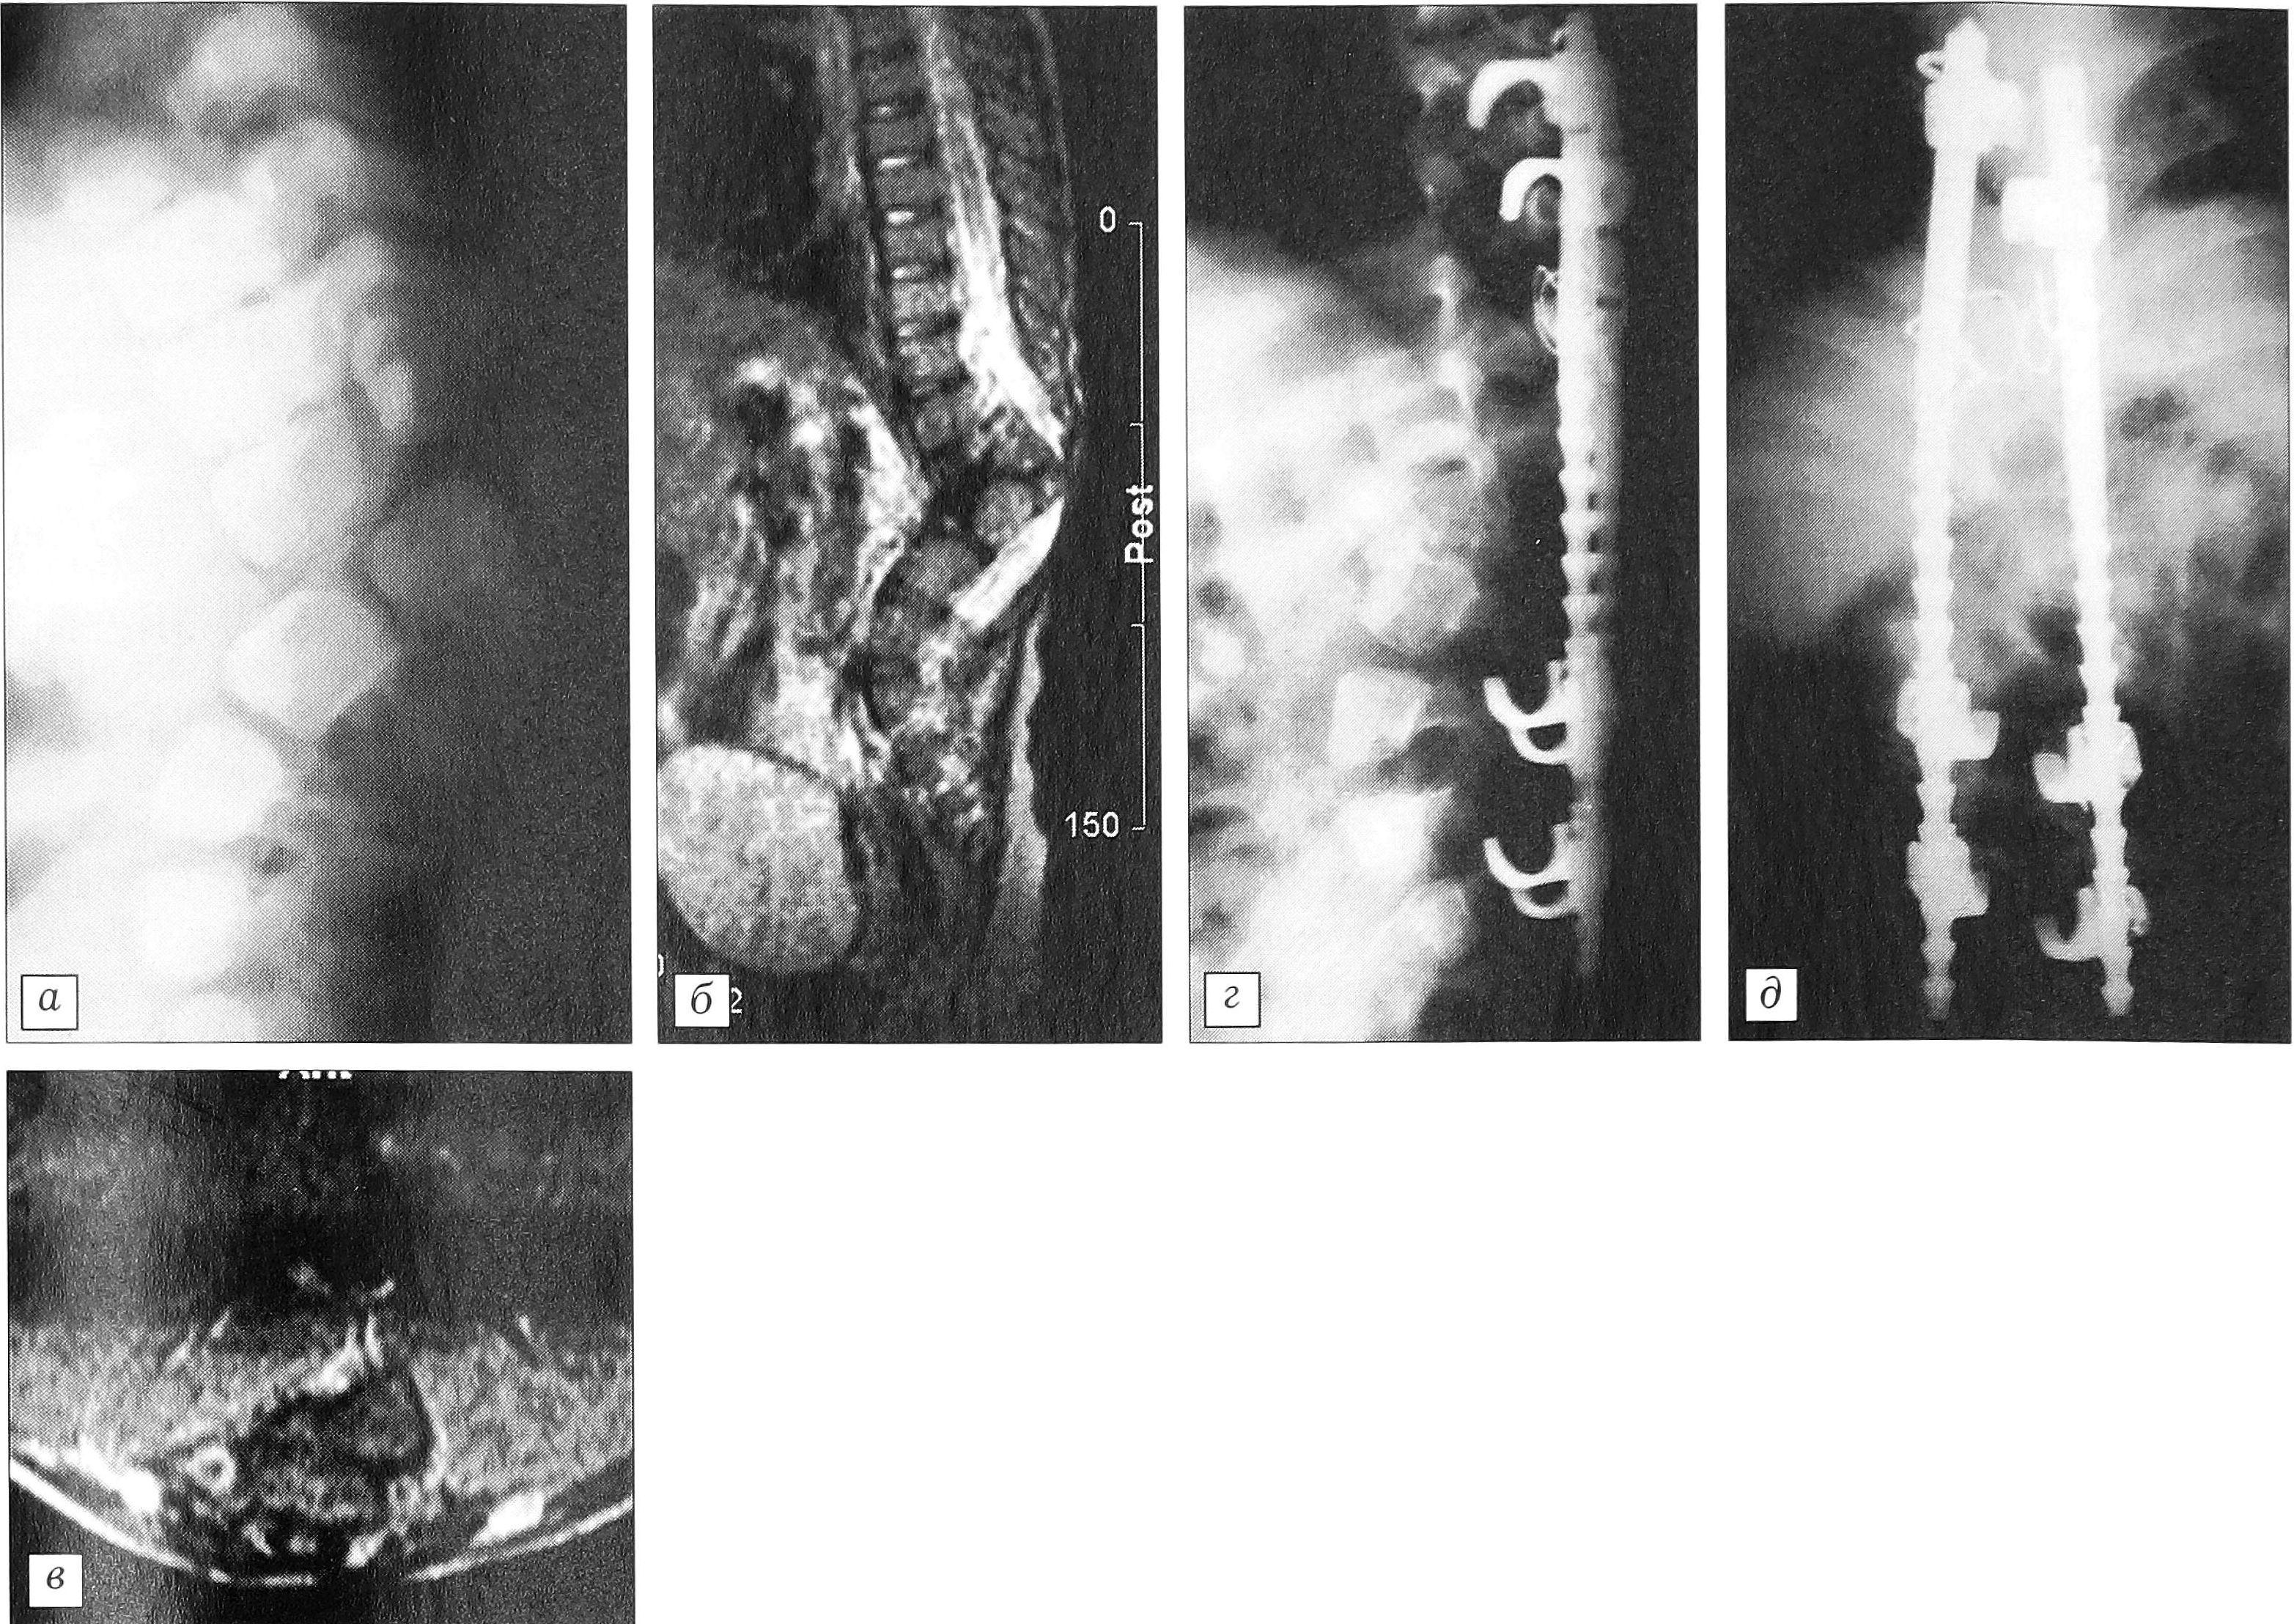

Лучевое обследование. Оценка переднезадних рентгенограмм невозможна из-за суммации теней костных структур, отчетливо видно лишь отсутствие бокового искривления позвоночника. На боковой рентгенограмме (см. рисунок, а) выявляется грубая кифотическая деформация — 63°. Краниальные сегменты позвоночника до уровня Т11 развиты нормально; тело Т12 обычных размеров, но не имеет дуги; кзади от него расположено тело L1, смещенное в позвоночном канале краниально до нижней трети тела Т11; еще более дорсально находится гипоплазированное тело L2. Дуги на уровне позвонков Т12- L2 отсутствуют, от L3 и каудальнее сохранены.

Данные МРТ подтверждают выявленные изменения. Хорошо видны резкая деформация и сужение позвоночного канала на вершине кифоза; дуральный мешок и спинной мозг на значительном протяжении визуализируются непосредственно под кожей (см. рисунок, б, в).

В результате вмешательства кифотическая деформация исправлена практически полностью (см. рисунок, г, д). Послеоперационное течение без осложнений на фоне антибактериальной терапии (препараты группы цефалоспоринов и фторхинолонов). Первичное заживление ран. Ребенок выписан на 21-й день после операции под наблюдение ортопеда по месту жительства. Изготовлен съемный корсет. К моменту выписки неврологический статус больного не изменился.

Больной Ч.Д. 2 лет 7 мес. Диагноз: сегментарная спинальная дисгенезия. а—в — перед операцией: а — боковая рентгенограмма позвоночника, б — среднесагиттальный MPT-срез, в — коронарный MPT-срез на уровне вершины деформации; г, д — после операции: г — боковая, д — переднезаднаяя рентгенограмма.